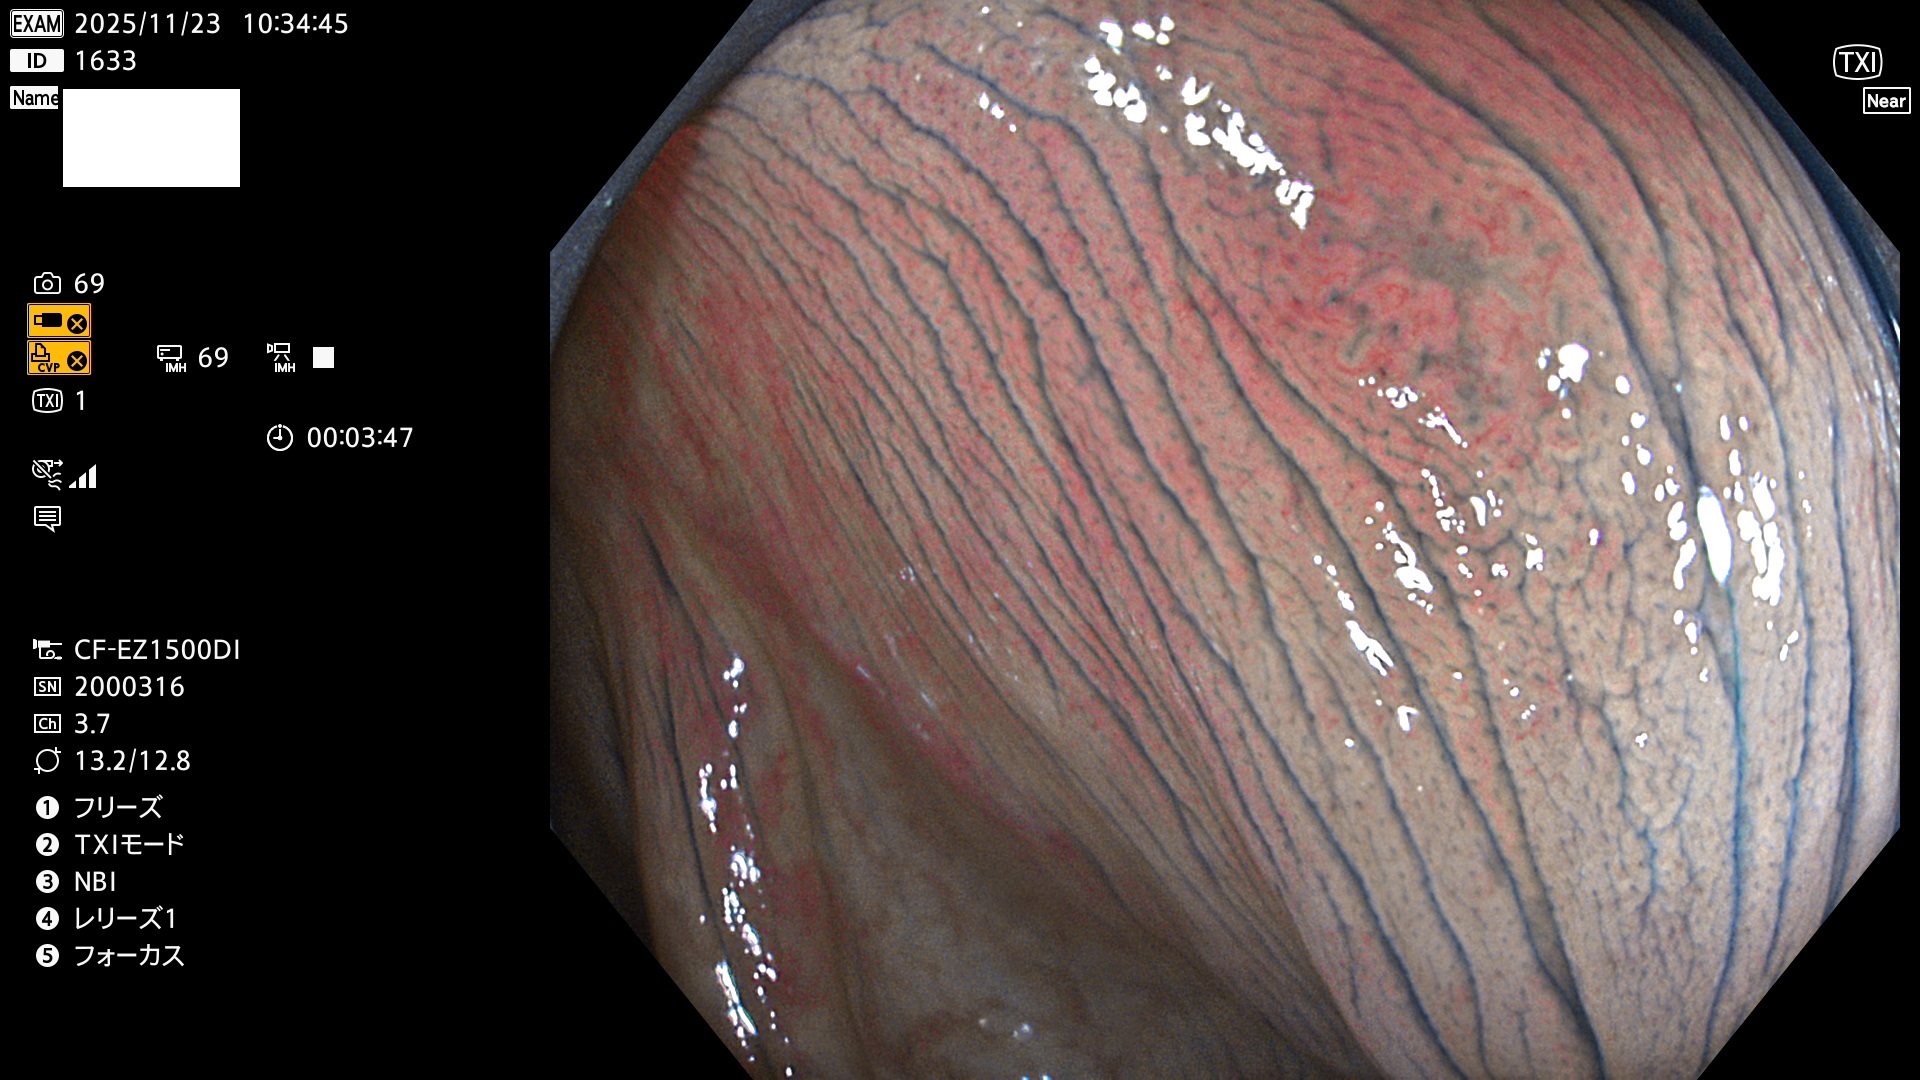

毎週の検査(木・金・土・日)に発見されたUbとUc型・腺腫を、その週の日曜の夜にUPし1週間、提示します。

写真公開の目的は「透明性・信憑性の担保」ですが、公開を希望されない方はメールで御連絡下さい。直ちに削除いたします。

2025年11月20日〜11月23日の4日間(40件)8個 (Uc_ADR=8個/40人=20%)